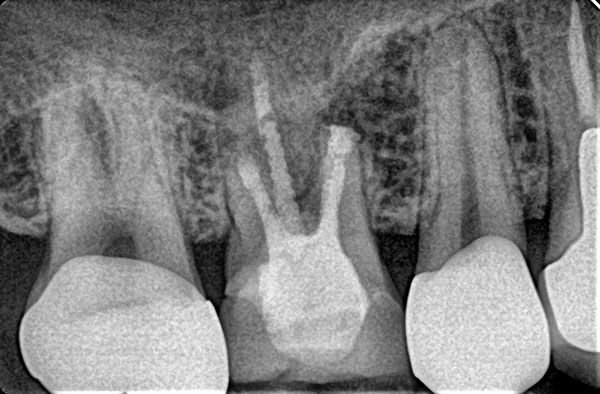

Пациентка Н. обратилась в мае 2023 г. с жалобами на периодические болевые ощущения в области жевательного зуба вверху справа. Анализ конусно-лучевой компьютерной томографии (КЛКТ) зубных рядов с помощью искусственного интеллекта (рис. 0) выявил наличие деструкции костной ткани в области верхушки мезиального корня зуба 1.6 с четкими контурами, при рентгенологически качественной обтурации корневых каналов (рис. 1). Такая картина не редка при необработанном перешейке между корневыми каналами, что крайне затруднительно при ортоградном доступе. При этом искусственная коронка изготовлена несколько лет назад.

После формирования слизисто-надкостничного лоскута по Ошенбейну-Любке (рис. 6), припасован хирургический шаблон для разметки участка остеоэктомии (рис. 5). В ходе работы получены точечные перфорации шнайдеровой мембраны (рис. 6), перекрытые коллагеновой губкой на время работы. Проведена резекция верхушки мезиального корня с ретроградным пломбированием под контролем операционного микроскопа. Создано второе окно остеотомии для превентивной апикальной микрохирургии и в области дистального корня. Контрольная интраоральная радиограмма зуба (ИРЗ) 1.6 от 15 мая 2023 представлена на рис. 7.

В динамике ИРЗ от 27 ноября 2023 представлена на рис. 8. В рамках ежегодной дентальной диспансеризации выполнена КЛКТ от 29 ноября 2023, на которой визуально отмечается наличие очагов радиолюценции в области верхушек щечных корней зуба 1.6 (по срокам соответствует периоду формирования слабо минерализованной костной ткани). В динамике на КЛКТ от 26 декабря 2024 визуально отмечаются признаки почти полного ее восстановления. Жалобы пациентки исчезли в ранние сроки после проведенной зубосохраняющей манипуляции и больше не проявлялись.